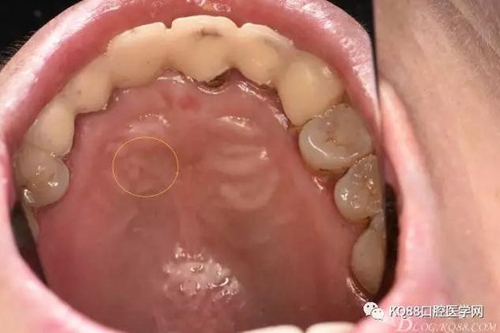

圖4.腭側(cè)觀:12根尖正對的腭粘膜隆起、有波動(dòng)感